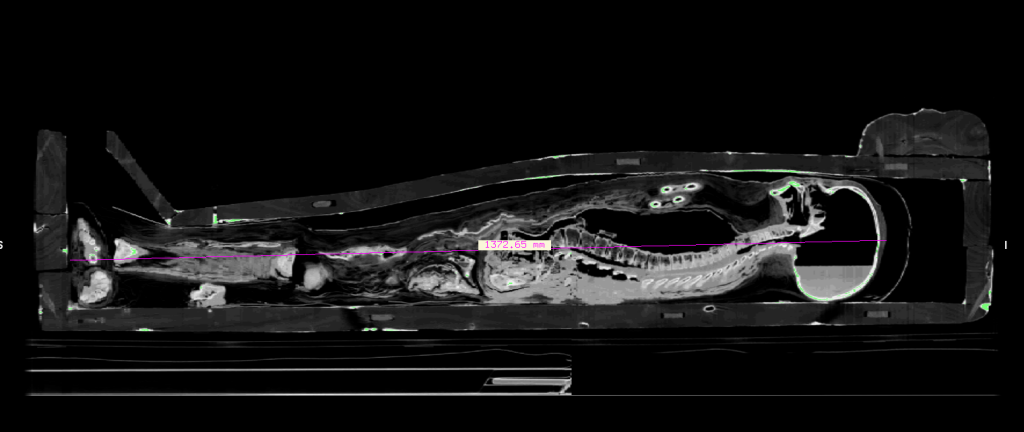

Por falar em ataúde, deu para ver os detalhes do madeiramento, tanto internamente quanto externamente.

Ao se filtrar os dados no InVesaius, ocultando a faixa correspondente a madeira, eis que o esqueleto lá dentro se revelou em 3 dimensões. As “impurezas” em volta do ataúde ao que parece trata-se do material de vedação entre uma madeira e outra.

Uma das características interessantes de uma tomografia é que ela podem vir na escala. No caso do menino tive que lançar mão das referências apresentadas no vídeo para colocá-lo na escala correta, e inclusive descobrir a sua altura desidratado, que é de 1.37m. A partir desse dado iniciei a estimativa da idade.